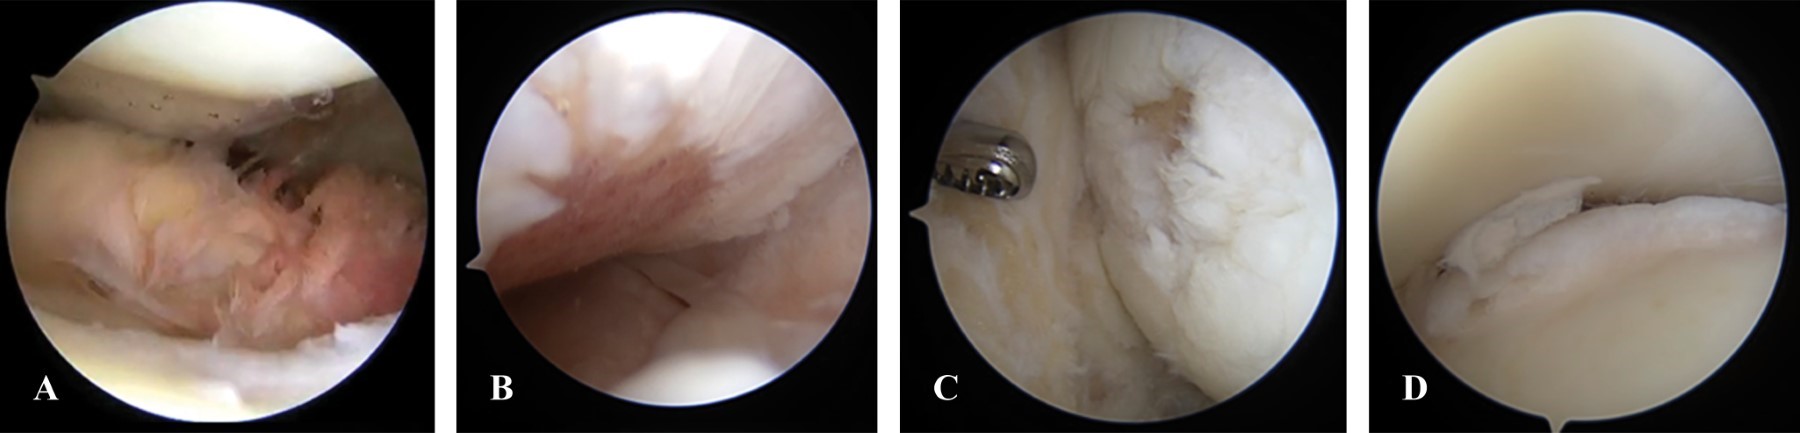

Se procede a realizar artroscopía, se evidencia: escotadura cerrada, ruptura completa inveterada de LCA, pinzamiento de LCP, ruptura del cuerno posterior y cuerpo de menisco lateral, ruptura crónica inveterada y extruida de menisco medial, pinzamiento femorotibial anterior, cuerpos libres intraarticulares, lesión condral de 1 cm2 en cóndilo femoral lateral en zona de carga, artrosis grado IV de compartimento medial de rodilla, sinovitis subcuadricipital (Figuras 4, 5, 6 y 7).

Durante la artroscopía, se realiza escotaduroplastía, liberación de LCP, desbridamiento de osteofito en espina tibial anterior, meniscectomía parcial de flap inferior del cuerno posterior y cuerpo de menisco lateral, meniscectomía parcial de raíz meniscal posterior remanente de menisco medial, extracción de cuerpos libres osteocondrales posteromediales, mediales y subcuadricipitales, remodelación de lesión condral en cóndilo femoral lateral en zona de carga, desbridamiento condral en periferia de cóndilo femoral medial (periartrosis), sinovectomía subcuadricipital (Figuras 4, 6, 7 y 8).